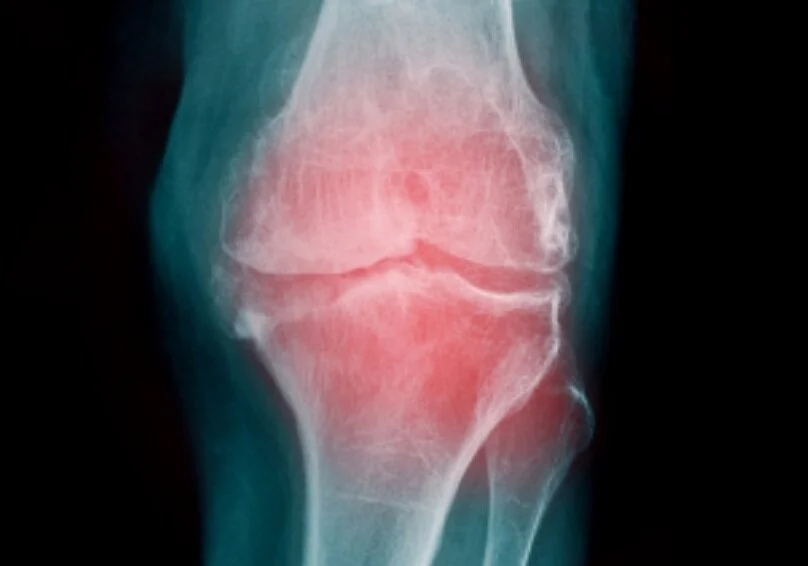

In episode 293 of season 7 we conclude our conversation with professor David Hunter of Sydney Australia. He shares more on the failures of the current common treatment and care. And, he shares what he’s an advocate for - a more active approach. Finally he offers helpful resources related to the data on osteoarthritis. This week on MCF!